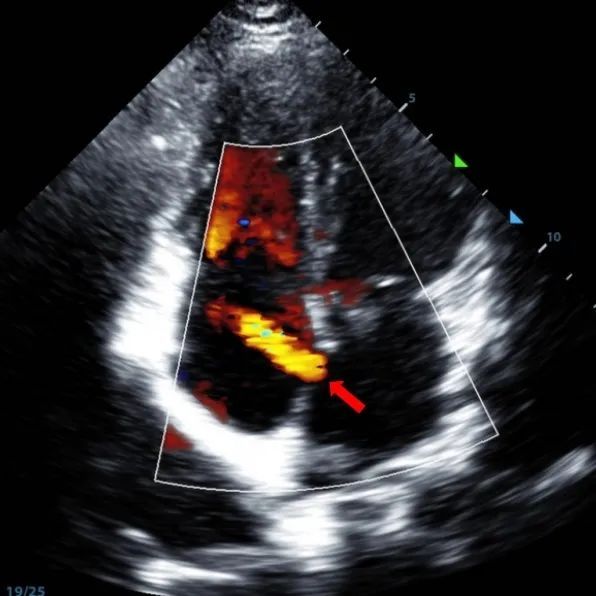

Un maschio di 9 anni con secundum ASD (7,5-7,9mm) è stato trattato utilizzando un sistema di occlusione da 12mm BDASD-I MemoSorb e un sistema di somministrazione 12F. Non sono state rilevate complicazioni o comorbidità prima della procedura.

Serial echocardiographic follow-ups showed stable device position and favorable cardiac remodeling. Gradual degradation confirmed the occluder's long-term safety and efficacy.